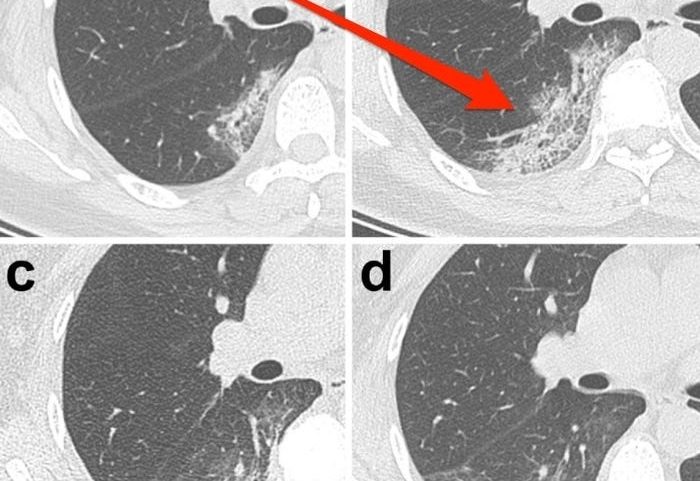

حلل الباحثون فحوصاً أجريت بالتصوير المقطعي المحوسب للمرضى بمستشفى في تشونغنان بجامعة ووهان، ومعظمهم من الرجال كبار السن الذين يعانون مشاكل صحية سلفاً. وتلك الصور أعلاه كانت لفحص مريض يبلغ من العمر 52 عاماً.

فقد صوِّرت المجموعة الأولى من فحوص التصوير المقطعي المحوسب في 7 يناير/كانون الثاني، بعد خمسة أيام من بدء ظهور الأعراض على المريض. وتظهر فيها بقع تشبه الزجاج المصنفر في قاع كلتا الرئتين.

إذ تلقَّى الرجل تدابير دعم الحياة في الفترة من 7 إلى 12 يناير/كانون الثاني، وبعدها ظهر التحسُّن على حالته. والمجموعة الثانية من صور الأشعة كانت في يوم 21 يناير/كانون الثاني، وتُظهِر تقلُّص أو اختفاء عديد من تلك البقع البيضاء.

وصلت امرأة تبلغ من العمر 33 عاماً إلى مستشفى بمدينة لانتشو بالصين، في حين تعاني الحمى والسعال منذ خمسة أيام، وكانت درجة حرارتها 39 مئوية، وكانت تعاني كذلك حشرجة في تنفُّسها، وانخفاض عدد خلايا الدم البيضاء، وهي إحدى علامات الإصابة بالفيروس. في الفحص المبدئي بالتصوير المقطعي المحوسب، وجد الباحثون بالمستشفى الأول في جامعة لانتشو بقعاً كالزجاج الأبيض في الزاوية السفلى من رئتيها.

أعطوها البروتين المستخدم لعلاج الالتهابات الفيروسية، ويسمى الأنترفيرون. ولكن بعد ثلاثة أيام -بالمضي قدماً في علاجها- كانت البقع أكثر وضوحاً، وقال لاكاني إن الشيء نفسه حدث لدى مرضى السارس. وقال: "إذا لم تكن على علم بهذا المرض، فستطالع الأشعة وستقول فقط: حسناً، هذا المريض مصاب بالتهاب رئوي، لأن هذا هو الشيء الأكثر شيوعاً من بين ما نرى".